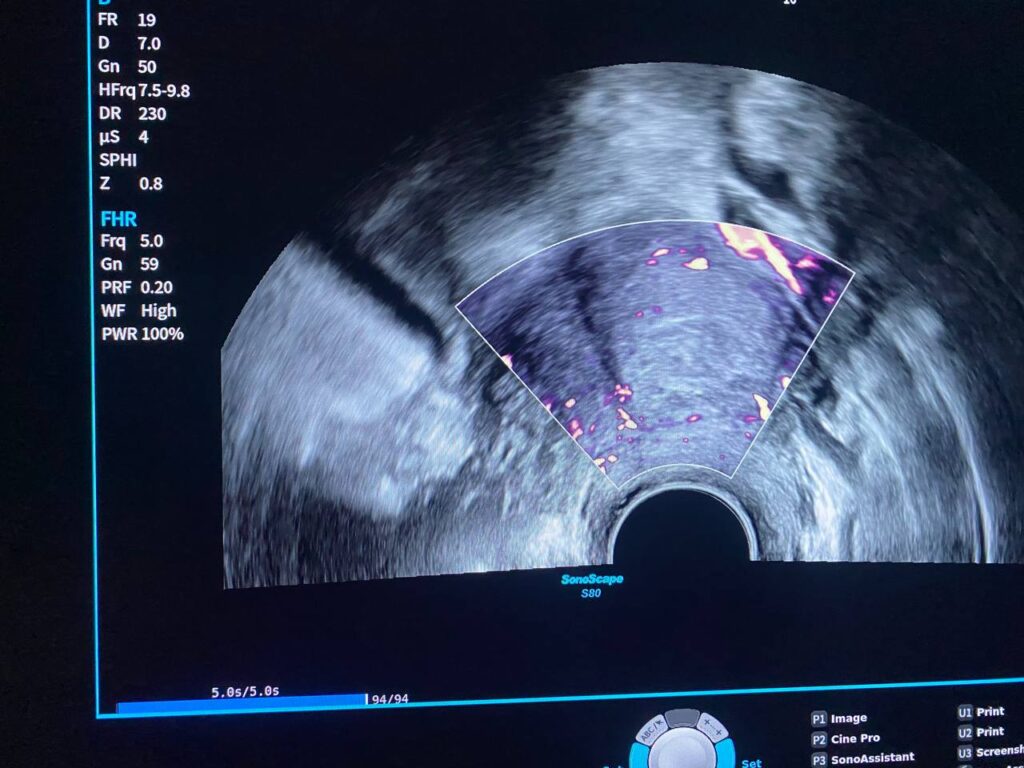

Presence of isoechoic heterogenous avascular area size 23x13x28mm, within the uterine cavity at level of internal os , mostly old retained piece of gestation, clear endo-myometrial junctional zone, no fibroid